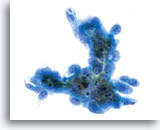

Glandulaire celclusters worden afgerond in PreservCyt-oplossing en kunnen uitschulpingen aan de randen van de groep vertonen. Let op de gladde, duidelijke cytoplasmische grenzen aan de rand van de groep.

40x